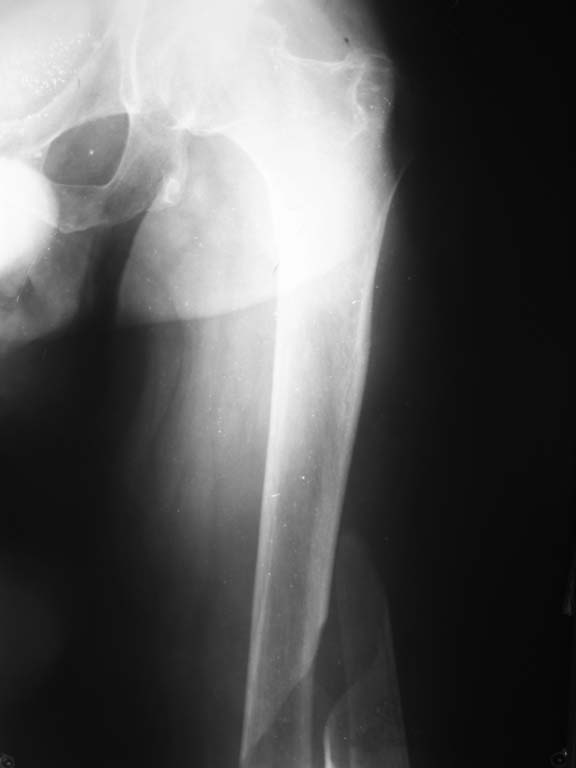

В отделение поступил больной 54 лет. Диагноз:закрытый перелом правой бедренной кости в/3 со смещением, закрытый перелом левой бедренной кости в с/3 со смещением. Посттравматическая клиновидная деформация тела Th11 позвонка(травма в 1991г),плегия н/конечностей, нарушение функции тазовых органов. Травму получил при пересаживании из коляски на кровать. Обследован, выявлены изменения в моче характерные для этой категории больных. Учитывая сопутствующую патологию и остеопороз планируем блокируемый остеосинтез стержнями максимального диаметра, соответствующих диаметру костно-мозгового канала. Уважаемые коллеги!Кто имеет опыт лечения данной травмы, пожалуйста, поделитесь возможными вариантами лечения.